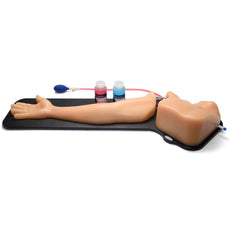

Arterial pulsations can help users differentiate between arteries and veins. Three arterial pulse configurations are available; no pump, hand pump, and integrated automated pump. Points of access include IJ, subclavian, infraclavicular and supraclavicular approach as well as access via the axillary vessel. Positive fluid flow in the vessels provides users with immediate feedback when vessels are accessed. The simulated blood fluids in the arterial vessels differ from the venous system allowing for users to easily differentiate between successful and unsuccessful venous access procedures.

Arterial pulsations can help users differentiate between arteries and veins. Three arterial pulse configurations are available; no pump, hand pump, and integrated automated pump. Points of access include IJ, subclavian, infraclavicular and supraclavicular approach as well as access via the axillary vessel. Positive fluid flow in the vessels provides users with immediate feedback when vessels are accessed. The simulated blood fluids in the arterial vessels differ from the venous system allowing for users to easily differentiate between successful and unsuccessful venous access procedures.

- Three arterial pulse configurations are available; no pump, hand pump, and integrated automated pump

- Positive fluid flow in the vessels provides users with immediate feedback when vessels are accessed

- Simulated blood fluids in the arterial vessels differ from the venous system allowing for users to easily verify successful venous access procedures

- Three arterial pulse configurations are available; no pump, hand pump, and integrated automated pump

- Positive fluid flow in the vessels provides users with immediate feedback when vessels are accessed

- Simulated blood fluids in the arterial vessels differ from the venous system allowing for users to easily verify successful venous access procedures